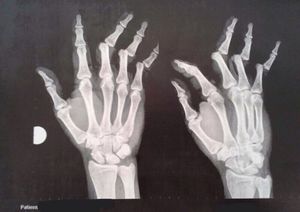

Multiple finger dislocations caused by a fall

Finger

Dislocation

Multiple